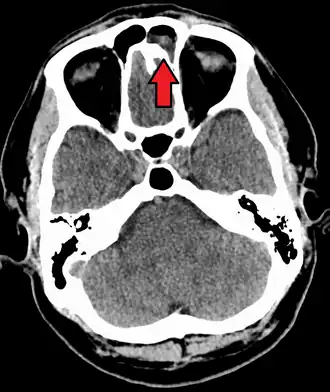

Imaging by either X-ray, CT, or MRI is generally not recommended unless complications develop.[66] Pain caused by sinusitis is sometimes confused for pain caused by pulpitis (toothache) of the maxillary teeth, and vice versa. Classically, the increased pain when tilting the head forwards separates sinusitis from pulpitis.[68]

For cases of maxillary sinusitis, limited field CBCT imaging, as compared to periapical radiographs, improves the ability to detect the teeth as the sources for sinusitis. A coronal CT picture may also be useful.[60]

Chronic

For sinusitis lasting more than 12 weeks, a CT scan is recommended.[66] On a CT scan, acute sinus secretions have a radiodensity of 10 to 25 Hounsfield units (HU). In a more chronic state, they become more viscous, with a radiodensity of 30 to 60 HU.[69]